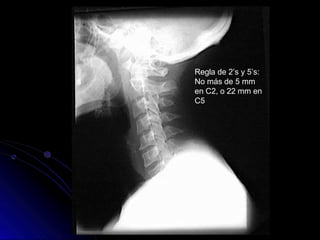

Partes Blandas Prevertebrales

● Espacio medido entre los cuerpos

vertebrales y la sombra de aire de la faringe,

laringe y tráquea.

● Normalmente 10 mm en C1

● 4-7 mm en C4 (retrofaringeal)

● 20-22 mm en C6 (retrotraqueal)

Regla de 2’s y 5’s:

No más de 5 mm

en C2, o 22 mm en

C5